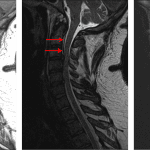

Age: 32

Sex: Male

Indication: Trauma, right occipital condyle fracture on prior CT

- Large right central disc herniation at C3-C4, which contacts and deforms the right ventral cord contributing to severe right eccentric spinal canal stenosis and effacement of the right subarticular zone

- Central cord signal abnormality at and just inferior to the C3-C4 disc herniation

- T1/T2 hyperintense ventral epidural collection spanning C1-C3, measuring up to 3 mm in thickness

- Small posterior disc osteophyte complexes and uncovertebral spurring at C4-C5 and C5-C6 contribute to mild spinal canal stenosis and mild left greater than right neural foraminal stenosis

- Mild left neural foraminal stenosis at C6-C7

- Traumatic disc herniation with spinal cord contusion

Age-indeterminate large right central disc herniation at C3-C4, which contacts and deforms the right ventral cord contributing to severe right eccentric spinal canal stenosis and effacement of the right subarticular zone. Cord signal abnormality at and just inferior to this disc herniation is concerning for contusion in the setting of trauma.

Thin ventral epidural hematoma spanning C1-C3, which measures up to 3 mm in thickness.

The reported right occipital condyle fracture is not well demonstrated on this study. Transverse and alar ligaments appear intact.